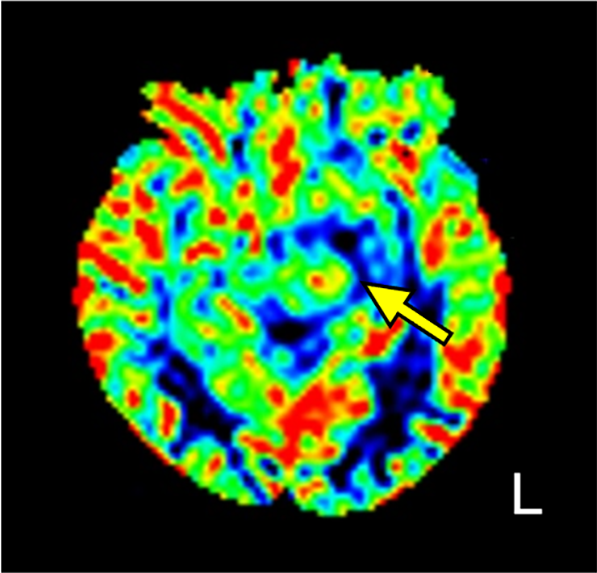

図4.ALS

病変の中心部に腫瘍血管も疑う点状の信号上昇を認める(矢印)。hyper vascu-larな病変を推測する。